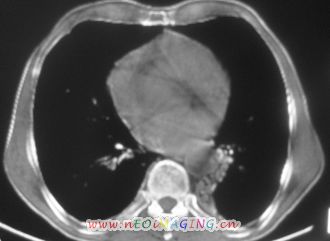

以下是引用卜一在2007-10-7 9:38:00的发言:[br]左下肺胸膜下团片影,内见含气支气管像,临近胸膜未见增厚。多考虑:1 左下肺炎症,建议消炎后复查!2 不除外肺隔离症合并感染!